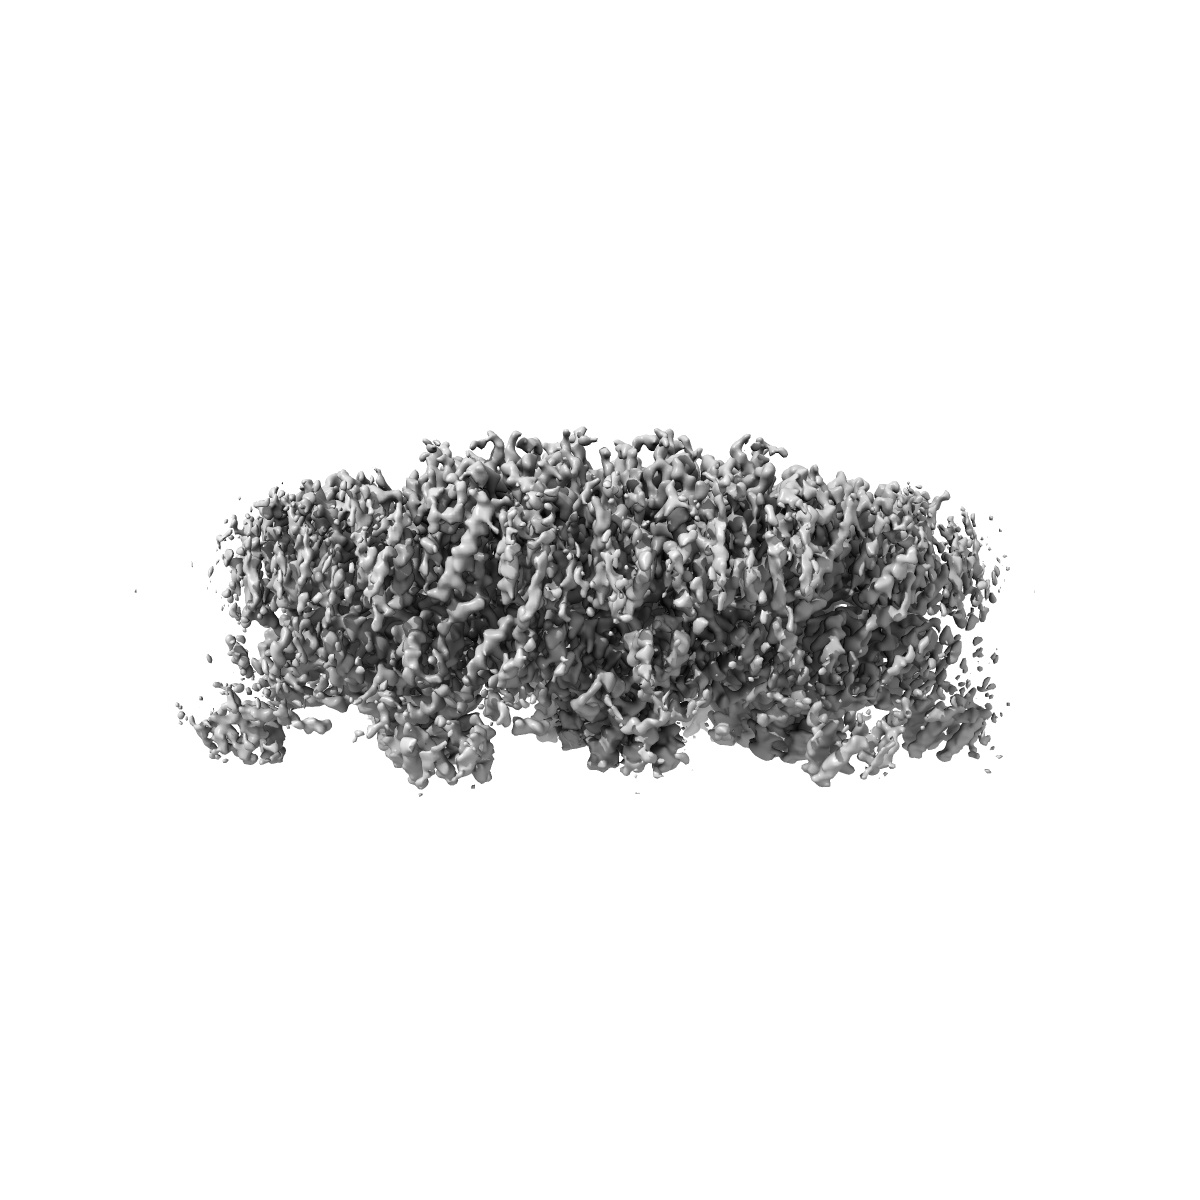

Gag CA-SP1 immature lattice bound with Lenacapavir from enveloped virus like particles (T8I)

Single-particle

3.13 Å

Structural insights into inhibitor mechanisms on immature HIV-1 Gag lattice revealed by high-resolution in situ single-particle cryo-EM.